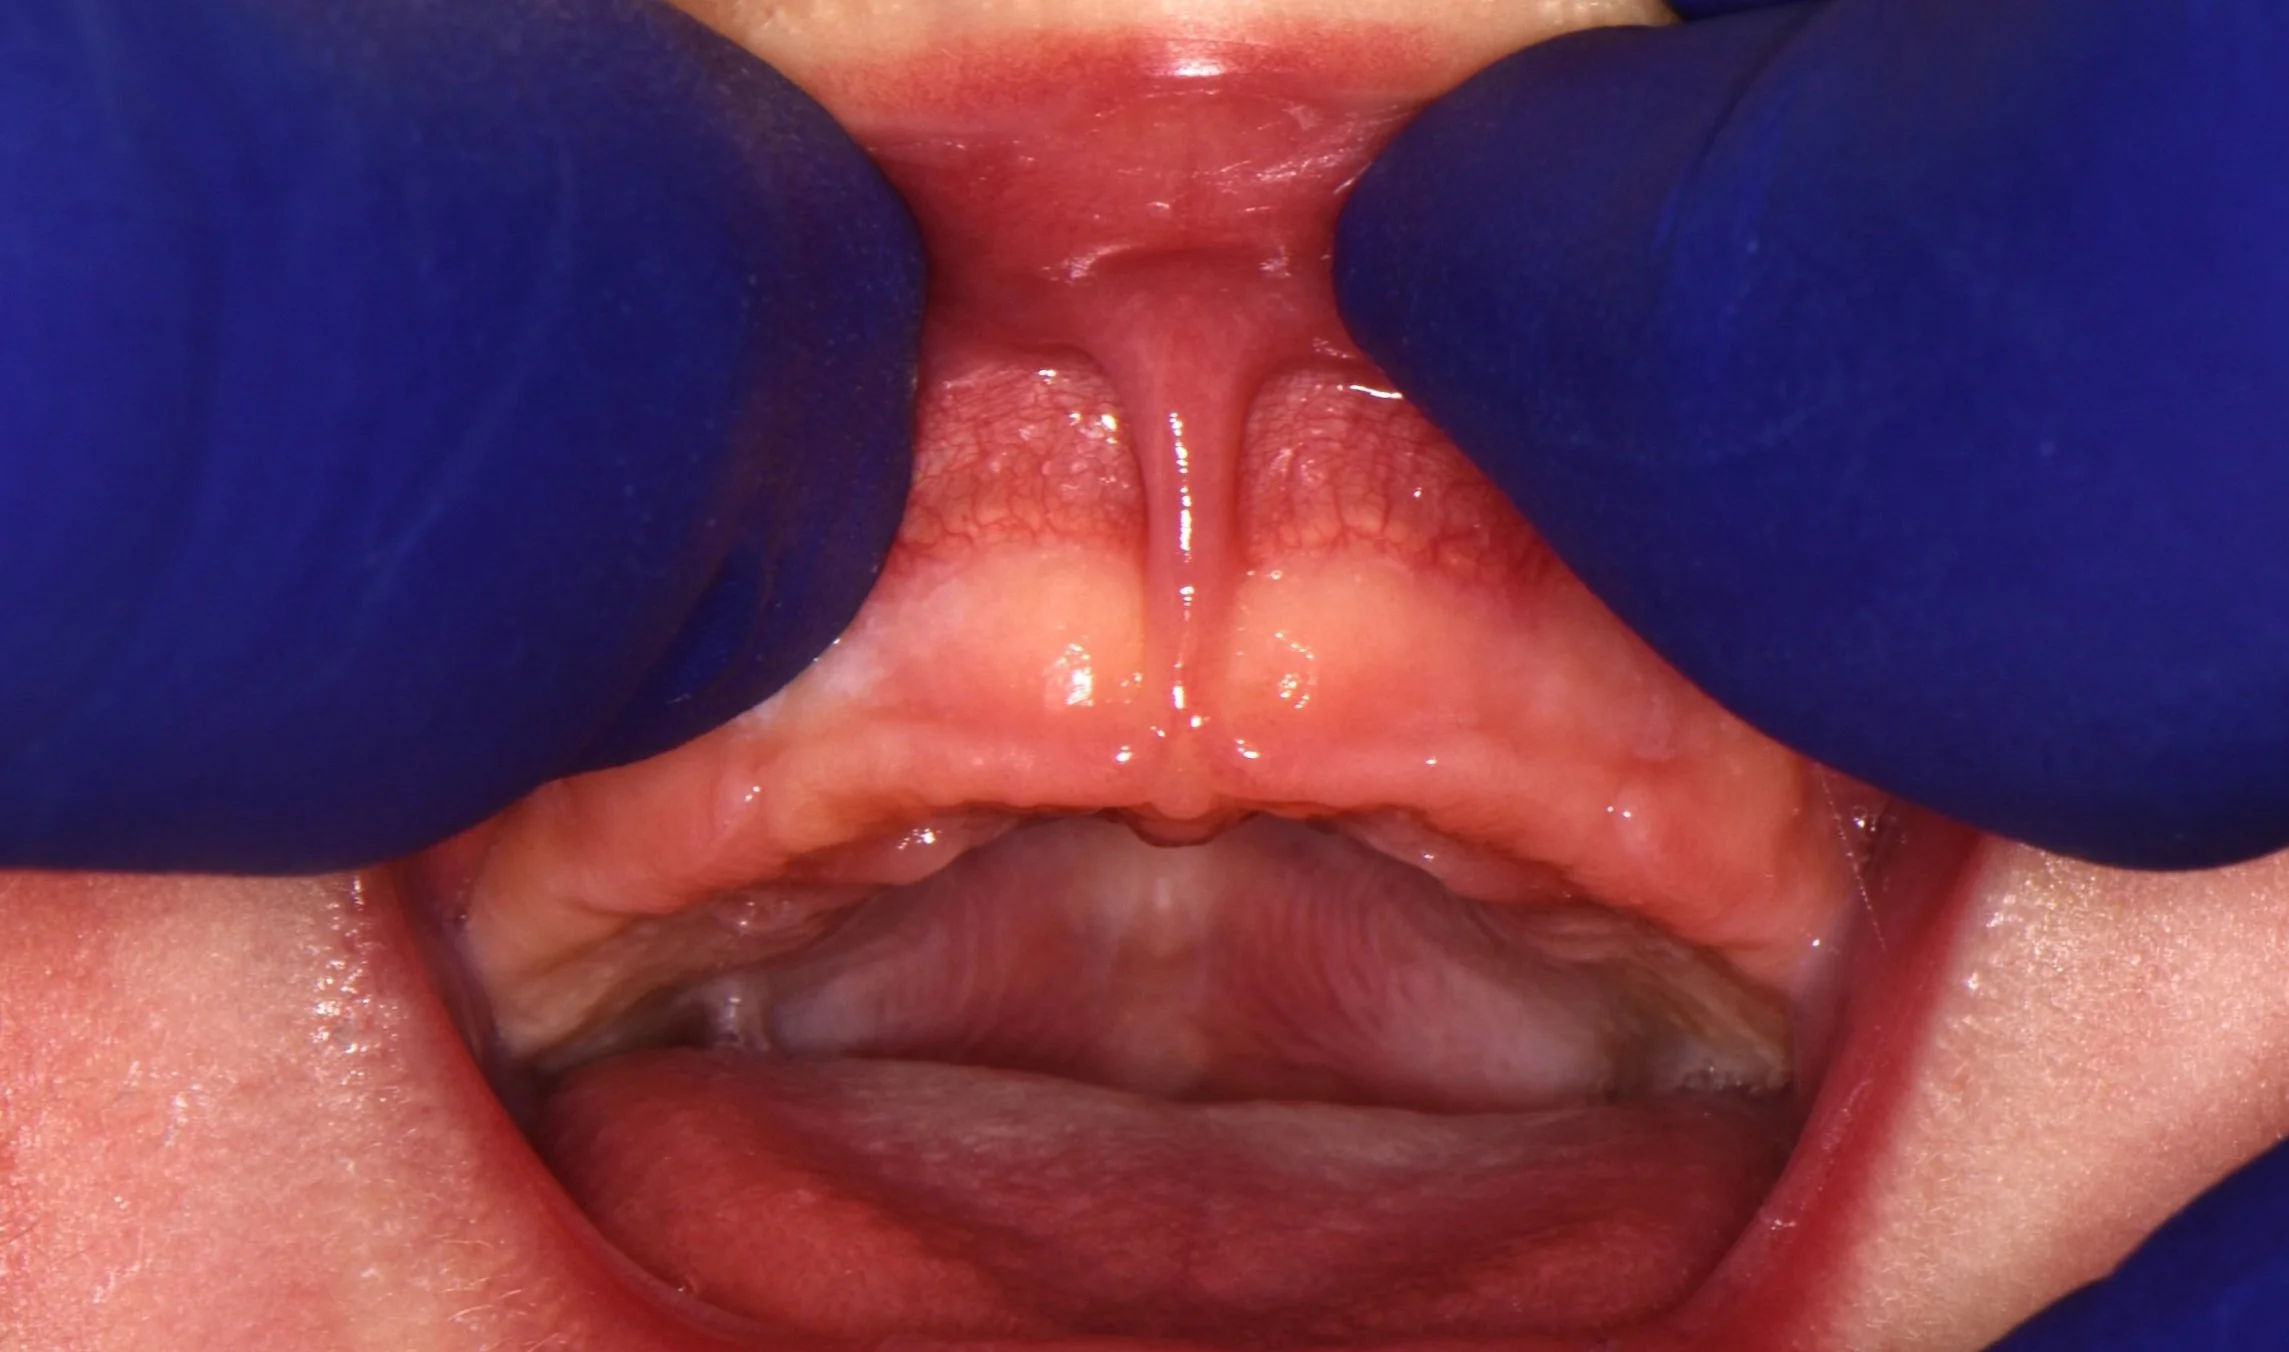

Photo of Tooth Socket After Extraction, Before Bone Graft

🦷 Step 2: Tooth Extraction

After gentle removal, the socket (the bony hole where the roots sat) is clearly visible.

Left alone, this socket starts to shrink immediately — studies show 30–60 % of ridge width can disappear within the first year after extraction (Araujo & Lindhe, Clin Oral Implants Res, 2005). That bone loss often makes future implants more difficult and can even affect facial contours.

Image:

The socket after gentle extraction.

*note for the adjacent tooth - we also did crown #19 that day, and this was before we cemented the temporary crown.

✅ Goal: Gentle extraction maintains socket integrity, keeping bone walls present, and prevents early bone collapse.